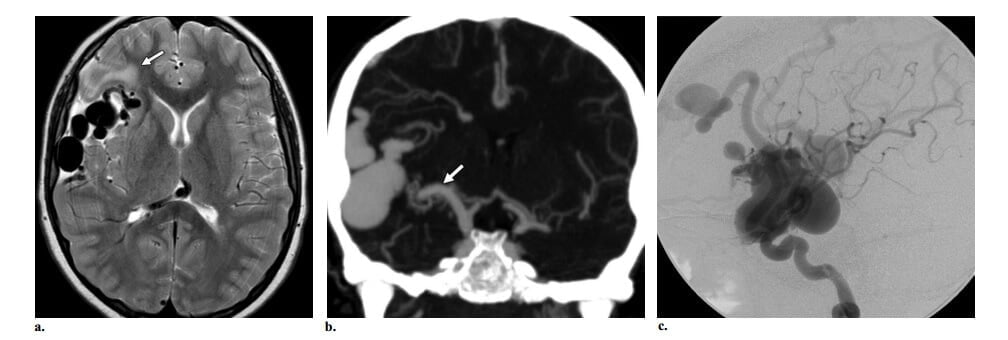

Manh mối để chẩn đoán AVF màng mềm trên hình ảnh cắt lớp gồm sự hiện diện của (a) các mạch máu dãn, chủ yếu ở bề mặt não; và (b) dãn bất đối xứng của động mạch nuôi màng mềm – hoặc là động mạch não giữa, não trước hoặc não sau- thường thấy rõ nhất ở vòng Willis. Các dấu hiệu này có thể dùng để phân biệt AVF màng mềm với AVF màng cứng (hình 9) và có thể đi kèm với túi tĩnh mạch dãn ở bên ngoài nhu mô não.

Hình 9: AVF màng mềm ở trẻ sơ sinh 1 tuần tuổi bị suy tim xung huyết. Bệnh nhân có bệnh sử gia đình dãn mao mạch xa xuất huyết di truyền. (a, b) Axial MRI T2W thấy lớn động mạch não giữa phải ở ngang mức vòng Willis (mũi tên ở a) và một cấu trúc mạch máu dãn lớn ở vùng quanh rãnh sylvien phải (đầu mũi tên ở b), dấu hiệu gợi ý túi tĩnh mạch. Phần trên của cấu trúc flow void lớn khác cũn g nhìn thấy ở hố sau. (c)Chụp động mạch cảnh trong phải thế nghiêng thấy dò dòng chảy cao giữa nhánh động mạch não giữa và túi tĩnh mạch lớn (đầu mũi tên). Dòng ngược chiều của thuốc cản quang đi vào động mạch thân nền khẳng định sự hiện diện của dò dòng chảy cao khác (mũi tên) từ động mạch tiểu não sau dưới. Dò dòng chảy cao và túi tĩnh mạch là các dấu hiệu điển hình ở bệnh nhân bị dãn mao mạch xa xuất huyết di truyền.

Tuy nhiên, điều trị có thể được chỉ định trong AVM không chảy máu và không cho thấy các điểm yếu cấu trúc mạch. Trong số đó, shunt dòng chảy cao có thể dẫn đến chậm phát triển tâm thần vận động và suy tim ở trẻ em, khi hiện diện ở người lớn có thể dẫn đến sa sút trí tuệ và vì vậy có chỉ định điều trị với mục đích làm giảm thể tích shunt động tĩnh mạch. Xung huyết tĩnh mạch do dòng vào cao (tổn thương dò) (hình 13) hoặc giảm dòng ra (hẹp thứ phát của dạng dòng ra ) có thể liên quan với suy giảm nhận thức hoặc động kinh; vì vậy, điều trị hướng đến việc làm giảm thể tích shunt động tĩnh mạch là cần thiết. Ngay cả nếu không có các dấu hiệu xung huyết tĩnh mạch, đường đi tĩnh mạch dẫn lưu màng mềm dài có thể chỉ ra rằng hạn chế dẫn lưu tĩnh mạch hiện diện qua một vùng lớn, làm tăng nguy cơ xung huyết tĩnh mạch và dẫn đến động kinh. Ngược lại, tĩnh mạch ngắn hầu như luôn luôn dẫn lưu trực tiếp vào xoang màng cứng có lẽ không ảnh hưởng đến dẫn lưu não bình thường. Nếu bệnh nhân có loại cấu trúc mạch này mà cũng có động kinh, thì hình ảnh MRI cẩn phải xem xét đến tăng sinh thần kinh đệm xung quanh nidus. Trong trường hợp đầu (bệnh nhân động kinh có AVM với tĩnh mạch dẫn lưu màng mềm dài), việc điều trị nội mạch bảo đảm để làm giảm sự cản trở dẫn lưu não bình thường và có lẽ để làm giảm tần số hoặc độ nặng động kinh; trong trường hợp sau (động kinh sau khi có tăng sinh thần kinh đệm quanh nidus), điều trị nội mạch có lẽ không làm thay đổi tần số và độ nặng của động kinh. Hiệu ứng choán chỗ là một cơ chế bệnh học hiếm gặp, có thể do dãn các tĩnh mạch lớn hoặc chèn ép các cấu trúc quan trọng bởi nidus và có thể dẫn đến động kinh, khiếm khuyết thần kinh và thậm chí não úng thủy. Cướp máu động mạch liên quan với các dấu hiệu lâm sàng (chẳng hạn, migraine và các triệu chứng thần kinh khu trú), thường chỉ có tính chất thoáng qua. Với sự đạt được của các phương pháp hình ảnh mới như MRI chức năng và hình ảnh tưới máu, hiện nay có thể xác định được các triệu chứng có thể được cho là do cướp máu thực sự hay không, điều đó có thể được điều trị bằng nội mạch với mục tiêu làm giảm thể tích shunt nếu triệu chứng không giảm.

Hình 13: AVF màng mềm có các túi tĩnh mạch và xung huyết tĩnh mạch ở bé trai 7 tuổi bị đau đầu. Bệnh nhân có bệnh sử gia đình chảy máu mũi và giãn mao mạch ở niêm mạc gợi ý dãn mao mạch xuất huyết di truyền. (a, b) Axial T2W (a) và chụp mạch Coronal CT (b) thấy cấu trúc mạch máu dãn, lớn trong vùng quanh rãnh sylvien hải gợi ý túi tĩnh mạch kèm lớn động mạch não giữa phải so với bên trái (mũi tên ở b) và không thấy nidus, các dấu hiệu phù hợp với AVF màng mềm. Tăng tín hiệu trên T2W ở chất trắng thùy trán phải (mũi tên ở a) gợi ý xung huyết tĩnh mạch. (c) Hình chụp động mạch cảnh trong thế nghiêng thấy dò dòng chảy cao giữa nhánh động mạch não giữa và các túi tĩnh mạch lớn.